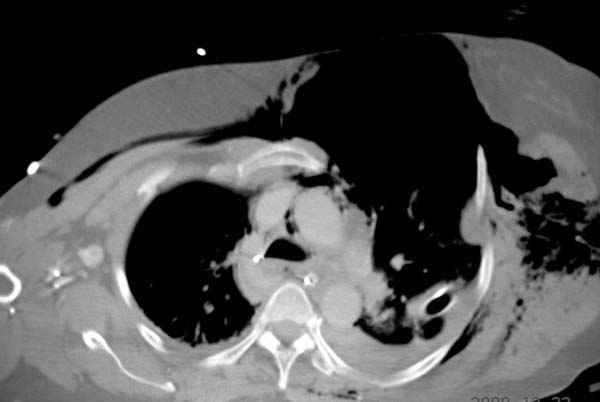

К нам поступила больная 56 лет после автоаварии в бессознательном состоянии, которая срочно заинтубирована в приемном отделении и сделаны необходимые исследования. Данные КТ и рентген показали перелом дистального бедра и Dissociation upper extremity - закрытый отрыв левой верхней конечности на уровне грудинно-ключичного сочленения и множественные переломы ребер.

На поверхности грудной клетки из-за полного разрыва грудной мышцы под кожей заметно биение сердца и след от ремня безопасности. Грудная клетка расширена из-за смещения верхней конечности вверх и латерально. Признаков васкулярного повреждения нет, и из-за отсутствия сознания не смогли определить наличия повреждения нервов.

После кожного разреза обнаружили полный разрыв грудной мышцы и повреждение перикард от уровня второго до восьмого ребер. Хирург находился с нами и после нашей работы зафиксировал повреждение перикарда и разрыв грудной мышцы.

Больная в данный момент с трахеостомой, стабильная, пришла в сознание. На сегодняшнем осмотре больная шевелит пальцами, что говорит об отсутствии повреждений нервов.